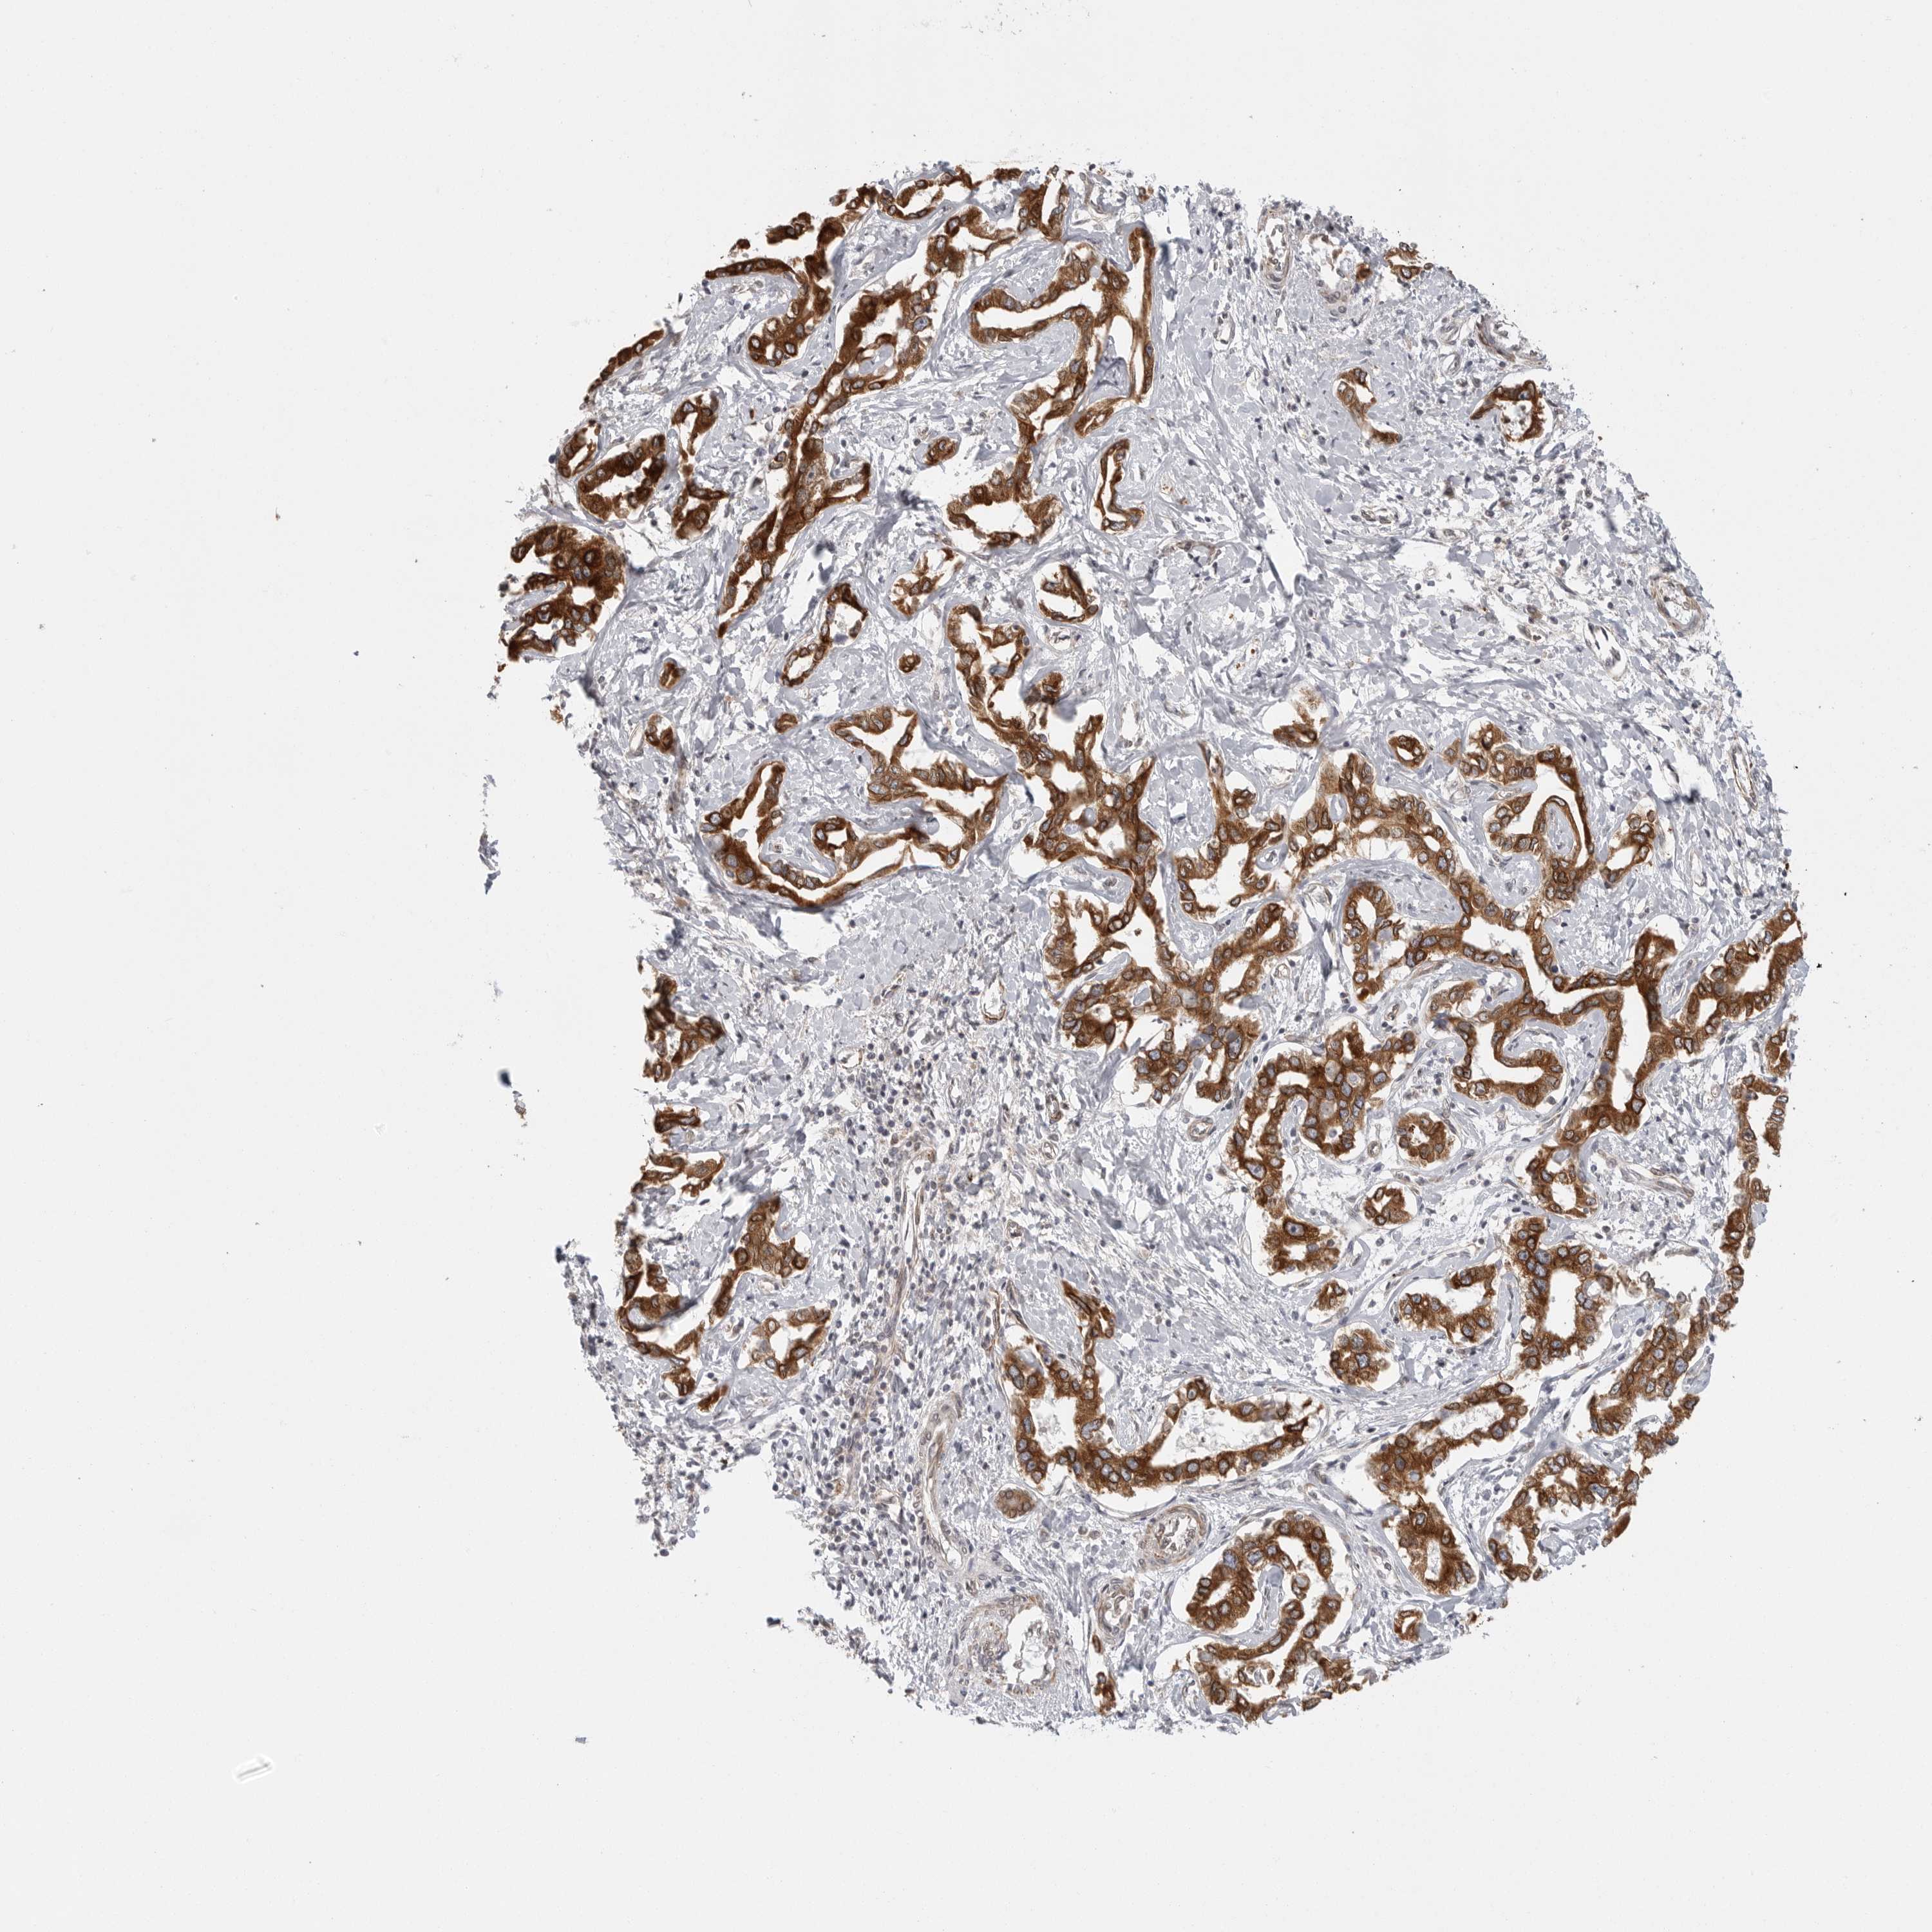

LIVER CANCER - Protein expressioni

A mouse-over function shows sample information and annotation data. Click on an image to view it in a full screen mode. Samples can be filtered based on level of antibody staining by selecting one or several of the following categories: high, medium, low and not detected. The assay and annotation is described here.

Note that samples used for immunohistochemistry by the Human Protein Atlas do not correspond to samples in the TCGA dataset.

Antibody stainingi

Antibody staining in the annotated cell types in the current human tissue is reported as not detected, low, medium, or high, based on conventional immunohistochemistry profiling in selected tissues. This score is based on the combination of the staining intensity and fraction of stained cells.

Each image is clickable and will lead to virtual microscopy that enables deeper exploration of all samples and also displays staining intensity scores, fraction scores and subcellular localization as well as patient and tissue information for each sample.

Antibody HPA027262

Antibody HPA078737

Staining

High

Medium

Low

Not detected

Intensity

Strong

Moderate

Weak

Negative

Quantity

>75%

75%-25%

<25%

None

Location

Nuclear

Cytoplasmic/membranous

Cytoplasmic/membranous,nuclear

Cholangiocarcinoma

Carcinoma, Hepatocellular, NOS